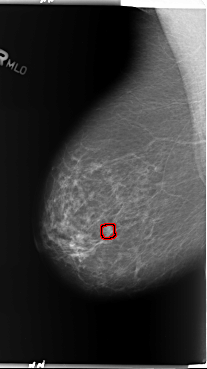

B_3362_1.RIGHT_MLO

RIGHT_MLO LINES 5896 PIXELS_PER_LINE 3312 BITS_PER_PIXEL 12 RESOLUTION 50 OVERLAY

FILE: B_3362_1.RIGHT_MLO.OVERLAY

TOTAL_ABNORMALITIES 1

ABNORMALITY 1

LESION_TYPE CALCIFICATION TYPE PUNCTATE-PLEOMORPHIC DISTRIBUTION CLUSTERED

LESION_TYPE MASS SHAPE ROUND MARGINS CIRCUMSCRIBED-ILL_DEFINED

ASSESSMENT 3

SUBTLETY 3

PATHOLOGY BENIGN

TOTAL_OUTLINES 1

BOUNDARY